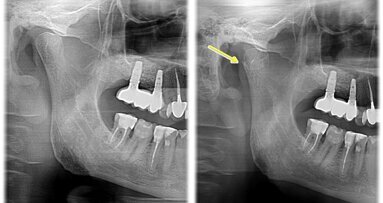

Ryc. 7_Stan 3 miesiące po zabiegu.

Ryc. 8_Zdjęcie pantomograficzne – stan 3 miesiące po zabiegu.

Kontrola została wykonana po 2 i 12 tygodniach po zabiegu. W tym czasie zaobserwowano gojenie się tkanek miękkich. Po 12 tygodniach wykonano badanie radiologiczne, które nie wykazało objawów zmniejszenia grubości blaszki kostnej, co mogłoby świadczyć o przewlekłym stanie zapalnym.